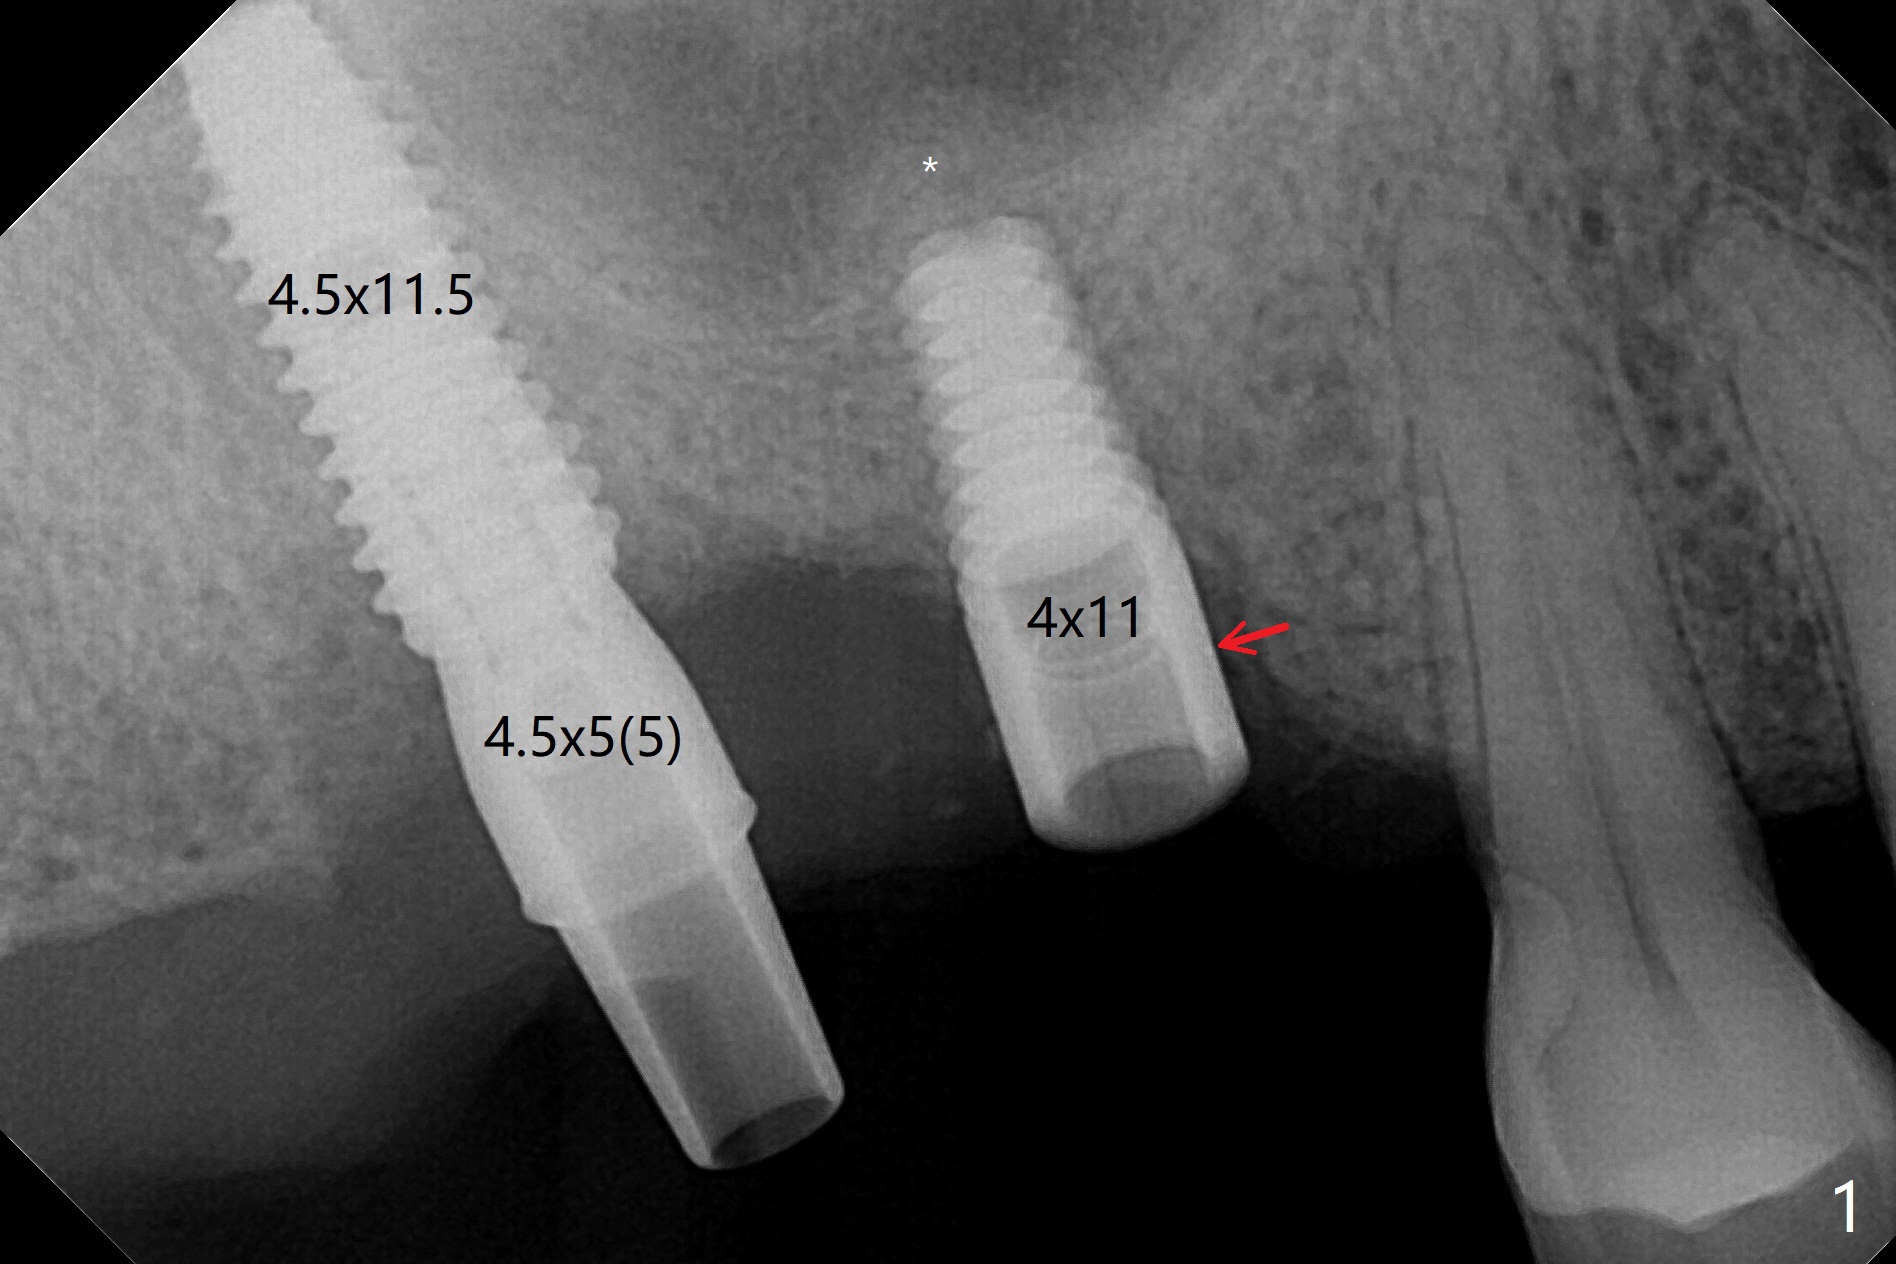

尽管2号牙植体比设计长,上颌窦提升顺利(图一,二)。虽然3号牙植体颊侧仍有骨质(图三:B),由于近中骨质多,徒手植入时植体远中偏移(图一:红箭头)。术后一个月树脂敷料撤除,2号牙牙槽窝,3号牙伤口愈合(图四)。